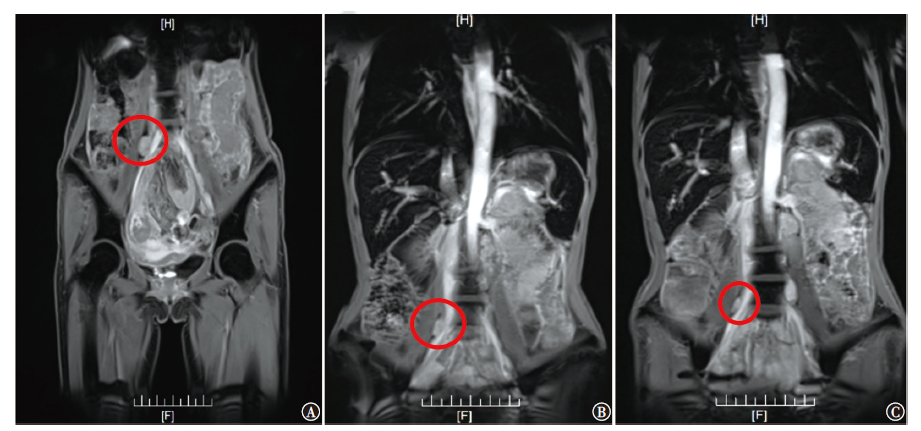

恶性腹膜间皮瘤是原发于腹膜间皮细胞的一种罕见恶性肿瘤,本例恶性腹膜间皮瘤晚期患者,通过特瑞普利单抗联合安罗替尼治疗后,CA125降至正常,病灶评估达到稳定,患者临床获益明显。该治疗方案对提高患者生命质量、稳定病灶起到了一定的作用。